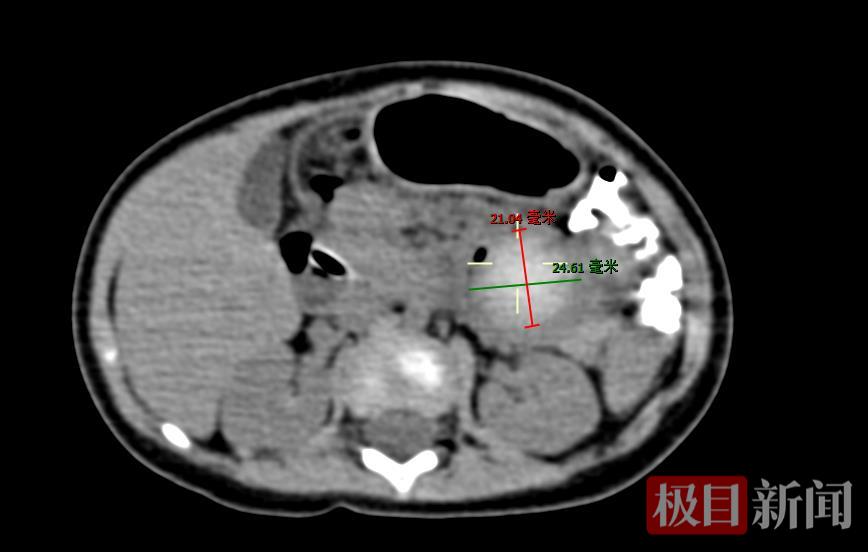

8个月大的恩施女婴晓晓是家中二宝,生得粉嫩可爱,平时吃奶、睡觉都十分配合,从不让爸妈操心。可十多天前,晓晓突然变得反常:莫名哭闹,进食后呕吐不止,起初是吐出白色奶汁,后来越吐越厉害,呕出黄绿色胆汁样液体,小肚子也胀得鼓鼓的。家人本以为是肠胃炎,可对症治疗后没有明显好转,当地医院进一步完善彩超及造影检查发现,晓晓的十二指肠内有“圆形充盈缺损影”,高度怀疑是误吞异物。

结合病史,晓晓被诊断为误吞异物导致的消化道梗阻。当地医生尝试在彩超引导下取物,可由于“水宝宝”位于十二指肠与空肠交界处,属于生理性的狭窄弯道,取出难度较大,多次尝试均未成功,医生建议手术治疗。